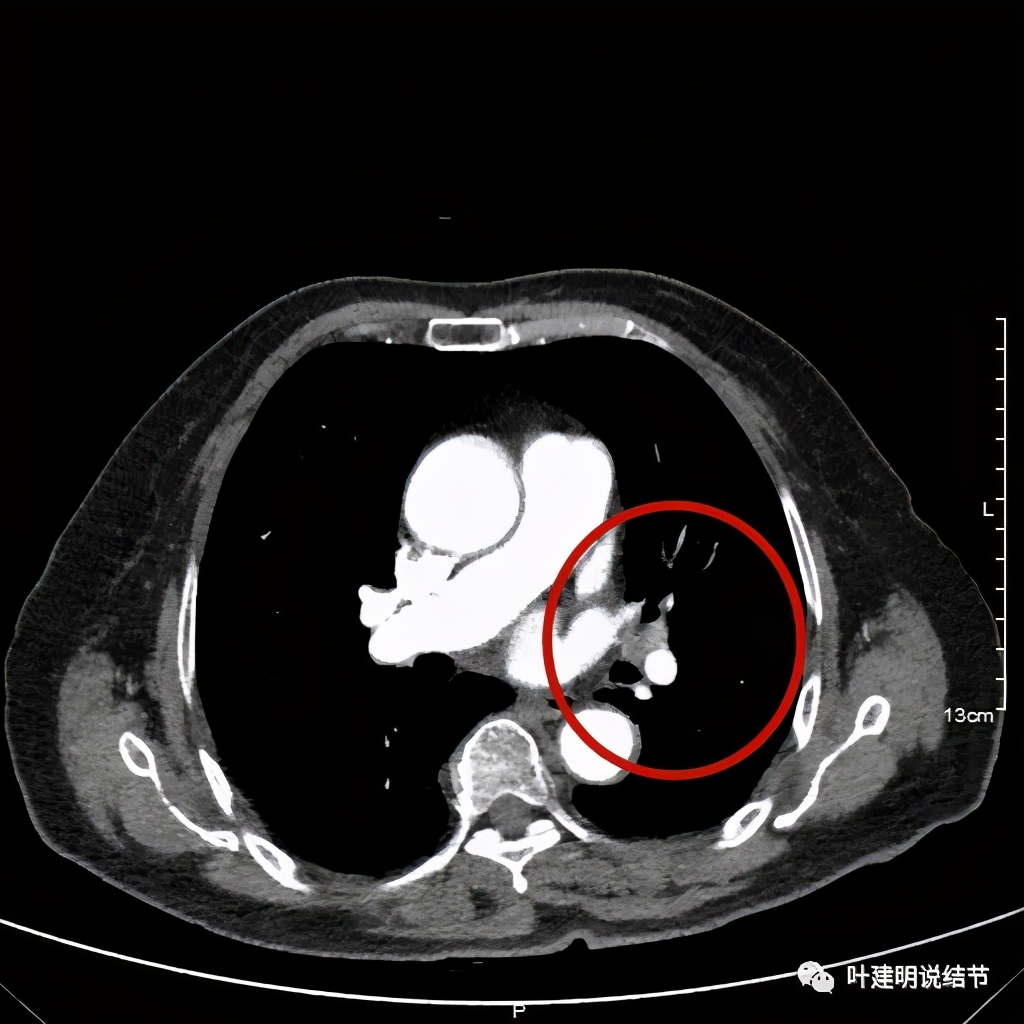

上图示主动脉弓水平仍见软组织影

上图桔色箭头示左肺动脉分支处仍被软组织(原肿瘤所在)包绕,粉色箭头示肺动脉仍与肿瘤处关系密切

上图也示桔色箭头示左肺动脉分支处仍被软组织(原肿瘤所在)包绕,粉色箭头示肺动脉仍与肿瘤处关系密切